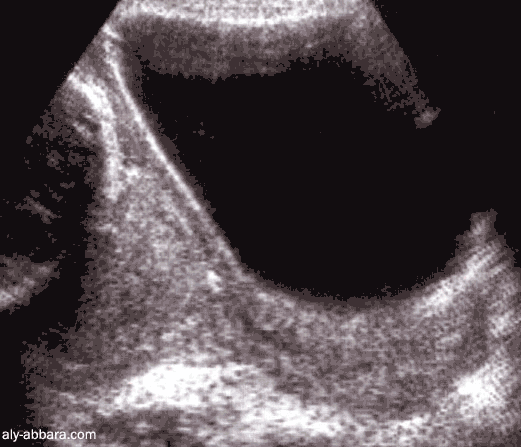

Placenta prævia, recouvrant postérieur (Type IV)

à 34 semaines d'aménorrhée

Cette image montre l'insertion anormale du placenta ; d'abord sur la paroi

postérieure du segment inférieur, puis sur l'orifice interne du col utérin et enfin

sur presque les deux tiers inférieurs de la paroi antérieure du segment inférieur